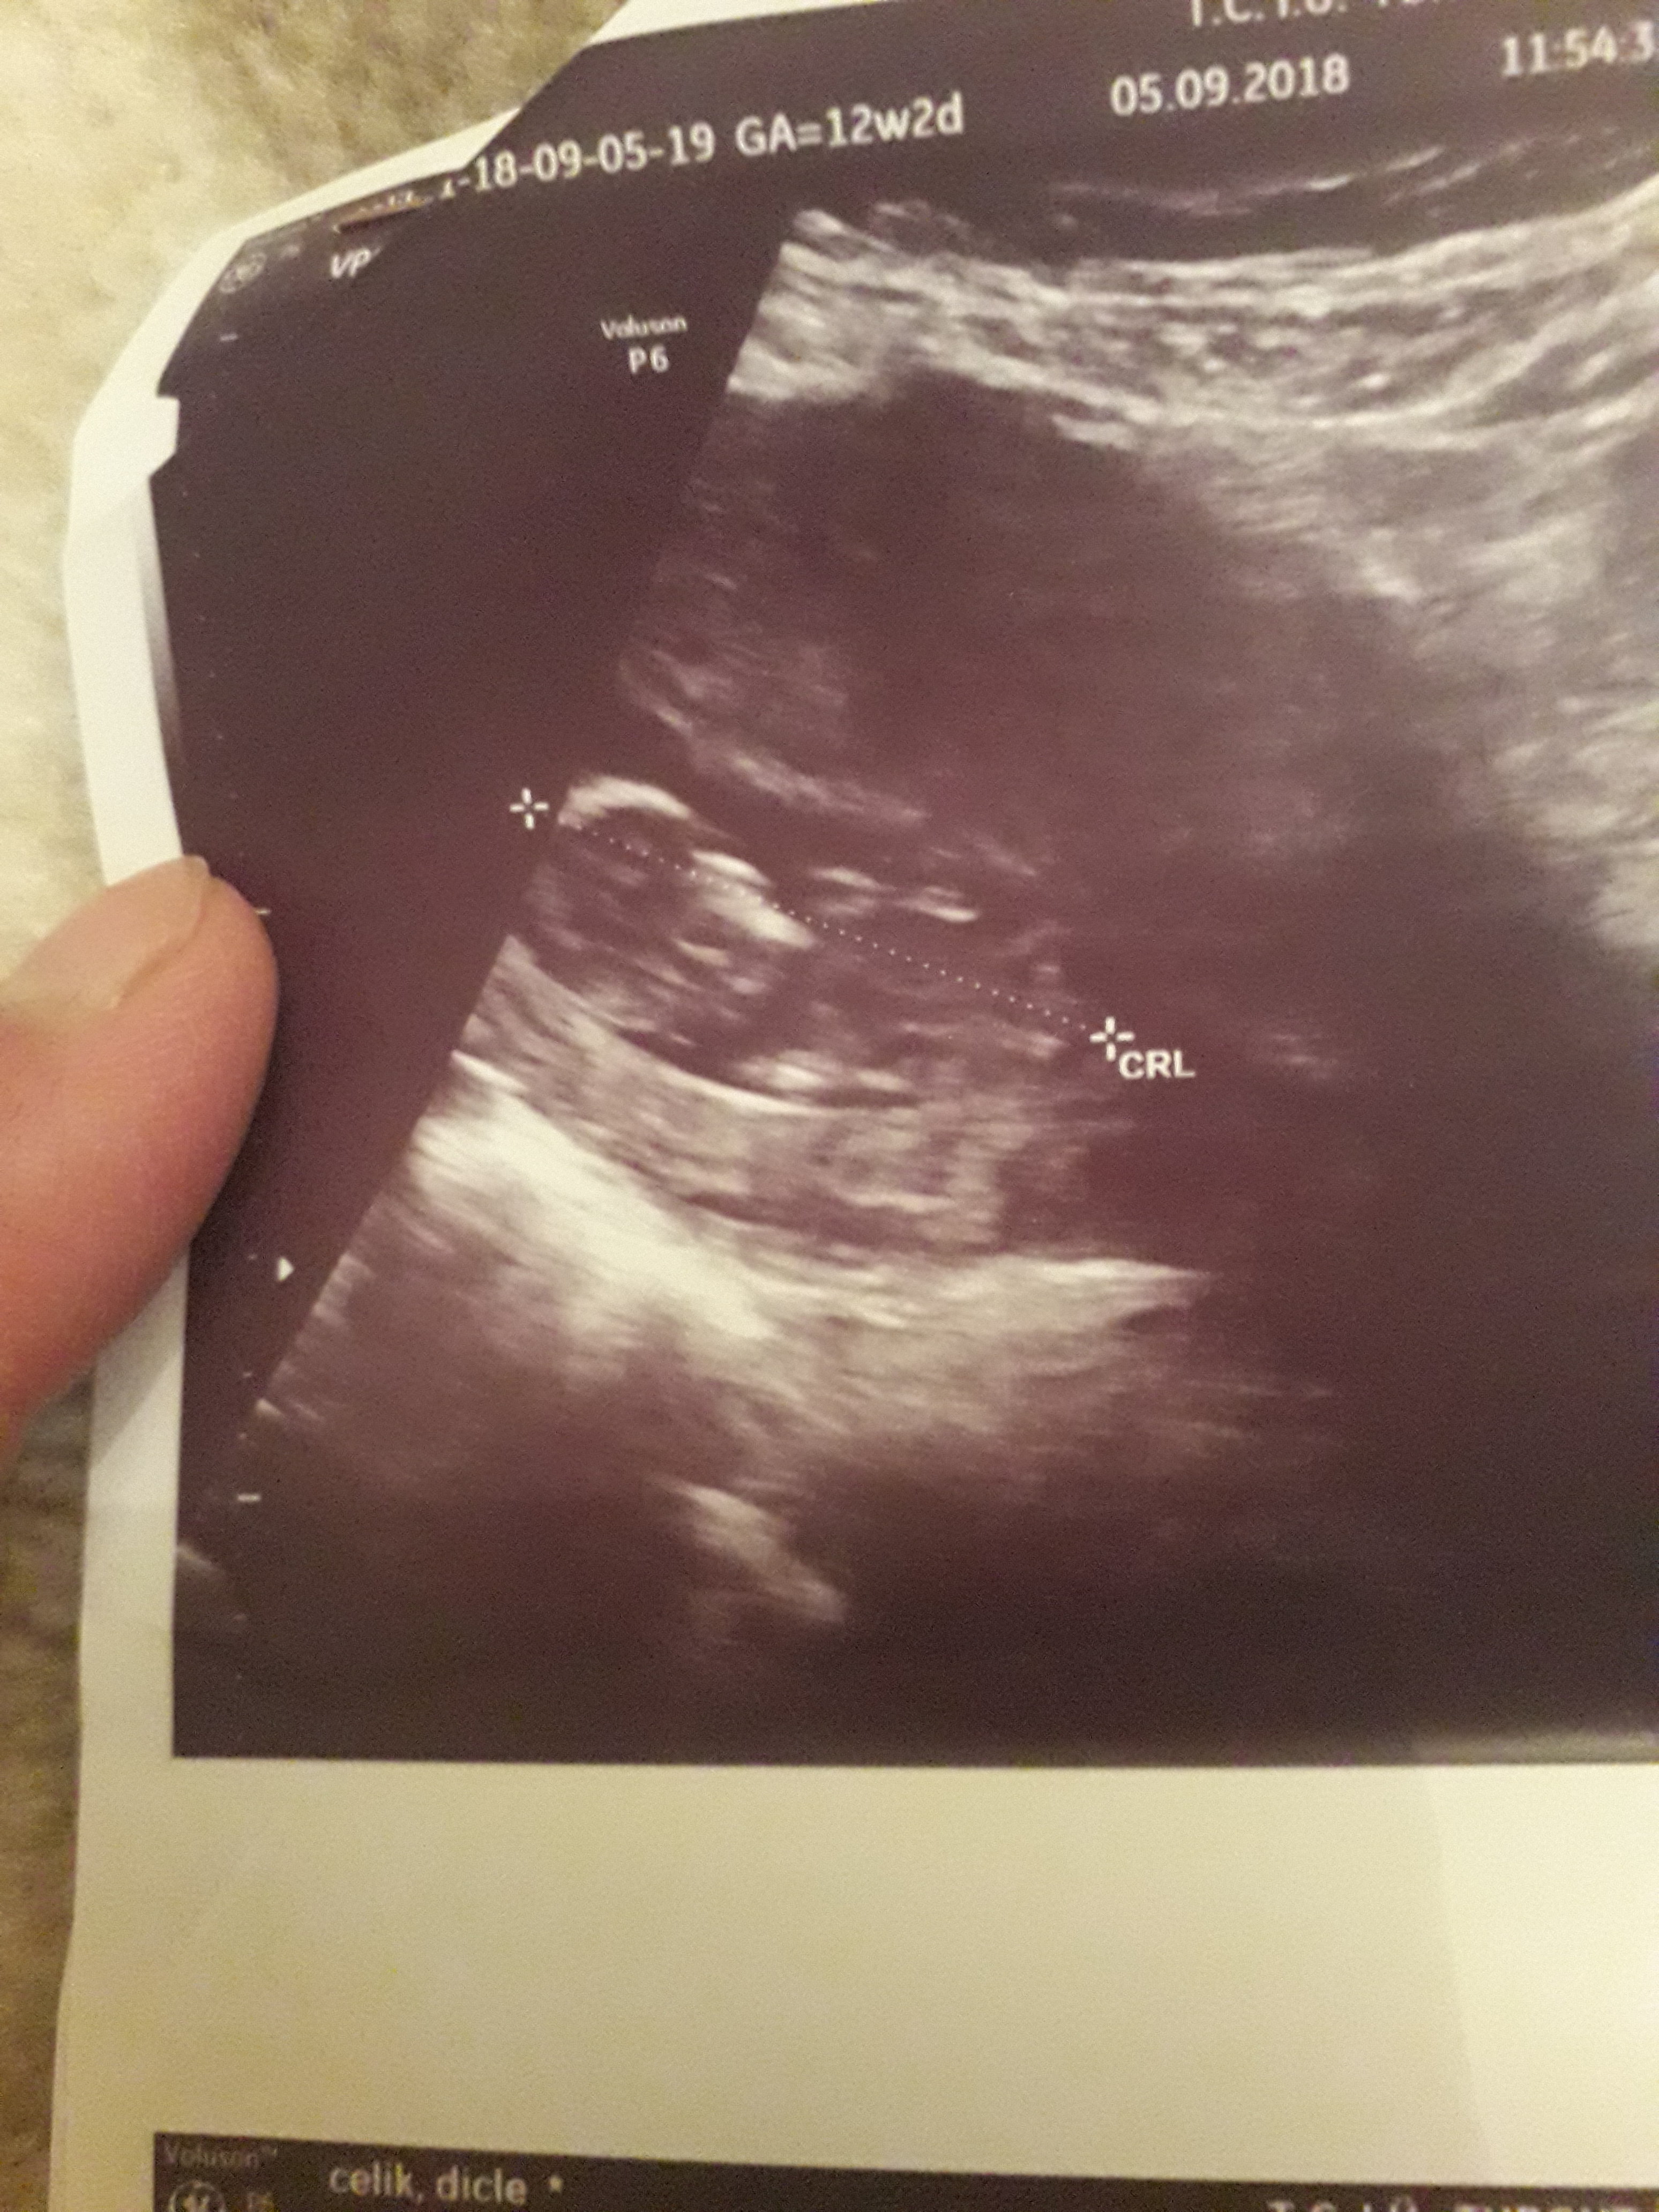

Dun malatyada verildi 12 +4 gunluk lutfen yorumlayin

nub çıkıntısının üzerinde imleç var cinsiyet anlaşılmıyor ilk sayfayı incelemenizi öneriyorum görselin kalitesi konu içinde yer alan görselle aynı olmalıdır.

Nub teorisiyle cinsiyeti uzman hekimler belirleyebiliyormuş. Bu yüzden doğruluk payı var.

Nub teorisi ile ilgili istatistiki bilgiler şöyledir;

1 hafta sonunda, doğruluk oranı 48 yüzde olduğu

12 hafta sonunda, doğruluk oranı 91 yüzde olduğu

13 hafta sonunda, doğruluk oranı 94 yüzde olduğu

Görsellerde nub çıkıntısı belli değil . Ultrasonu yapan doktor cinsiyeti hakkında bilgi vermiştir mutlaka ama şunu belirtmeden geçmeyeyim. Bu haftalarda cinsiyet tahmininde yanılma payı çok yüksek 17-19 ve 20 ci haftalarda bebeğin cinsiyetini net olarak öğrenebilirsiniz.